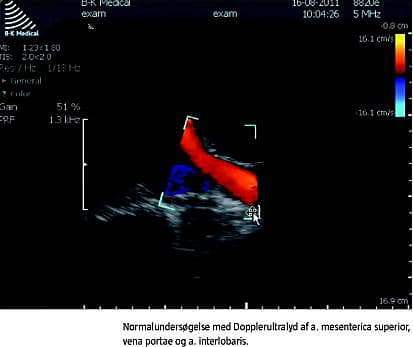

Nedenfor er givet eksempler på undersøgelser af abdominale kar med Dopplerultralyd. Ved undersøgelserne er der benyttet en lavfrekvent kurvet abdominaltransducer, og B- mode -billedet er optimeret mht. dybde, gain og fokus.

Arteria mesenterica superior

I faste har arteria mesenterica superior plug flow med en trifasisk profil, som ligner den i aorta abdominalis med hurtige op- og nedslag i systolen (Figur 3 ). Plug flow opstår, når blodet har omtrent samme hastighed, hvad enten det befinder sig i centrum eller mere perifert i karlumen. Spektralkurven er derfor skarpttegnet og overvejende uafhængig af range gate -bredde [4, 7]. Den trifasiske flowprofil skyldes, at der i tidlig diastole er et retrogradt flow og i sen diastole et antegradt flow. Efter fødeindtag sænkes modstanden i karret, og en øget maksimal systolisk hastighed (PSV) og slutdiastolisk hastighed (EDV) indtræder med udelukkende positivt flow i diastolen for at imødegå det øgede iltkrav fra tarmen. Flowprofilen ændres fra plug flow til laminart flow, der er kendetegnet ved faldende hastigheder i lumen fra centrum mod periferien, hvilket resulterer i en bredere spektralkurve [6, 8]. Ved betydende stenose i arteria mesenterica superior som ved kronisk intestinal iskæmi ses hos fastende patienter PSV > 275 cm/s, som øges yderligere postprandialt, samt EDV > 50 cm/s. Normalværdien ved faste er for PSV 130 (± 18) cm/s og EDV 24 (± 4) cm/s [7].

Vena portae

Flowet i vena portae estimeres med transduceren placeret interkostalt i patientens højre flanke. Herved opnås en brugbar insonationsvinkel, og overlejrende tarmluft undgås. Ved normalt flow i vena portae vil farve-Doppler inden for colour box vise antegradt (hepatopetalt) flow. Dvs. at flow i det portale system, der løber ind i leveren ved interkostal skannerposition, derfor bevæger sig mod transduceren. Range gate placeres i lumen og indstilles tilstrækkeligt smal, så signal fra arteria hepatica, der forløber i tæt relation hertil, undgås. Flowet er positivt og laminart med hastigheder på 20-40 cm/s. Der ses en diskret fasisk bevægelse i flowet synkront med hjertefrekvensen, hvilket skyldes tilbagetransmitterede trykændringer fra højre atrium via levervenerne, og en langsommere fluktuation, som skyldes respirationssynkrone trykændringer i thorax (Figur 3) [5].

Nyrekar

RI er en ratio, dvs. uden benævnelse og følgelig vinkeluafhængig. RI, der beregnes ud fra spektrogrammet og ofte automatisk af skanneren, er et udtryk for karrets komplians og modstand. Normalværdien for RI er 0,60-0,70 [6, 9] (Figur 3).